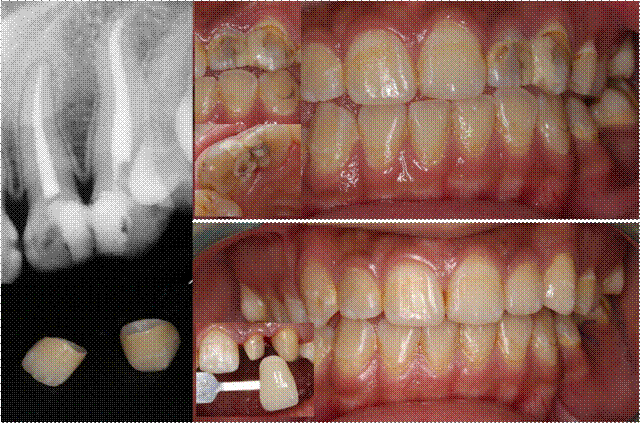

冷光美白术对于着色牙、轻中度四环素牙、氟斑牙等具有很好的美白效果。

图:重度四环素牙的冷光美白(连续两次治疗效果)